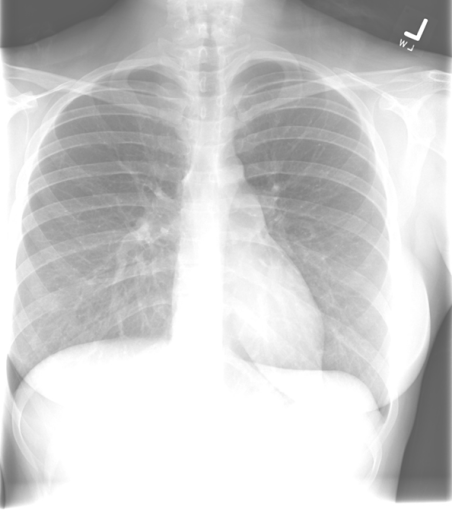

Inspiration

Deeper inspirations show more lung and result in better overall images with less haziness at the lung bases and less enlargement of the heart and mediastinum. A good inspiration on a PA CXR shows at least 9 posterior ribs.

The following films were of the same patient and taken using the same AP projection. The image on the left is a poor inspiratory effort (ribs 1-6), while in the film on the right, the patient achieved a much deeper inspiration on the bottom xray (ribs 1-10).

Poor Inspiratory Effort Good Inspiratory Effort